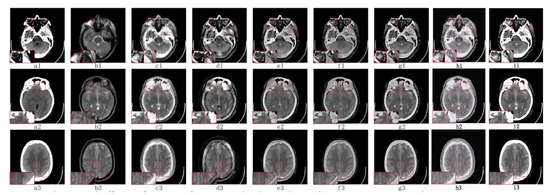

5.2.3. Fusion Analysis on CT-MRI